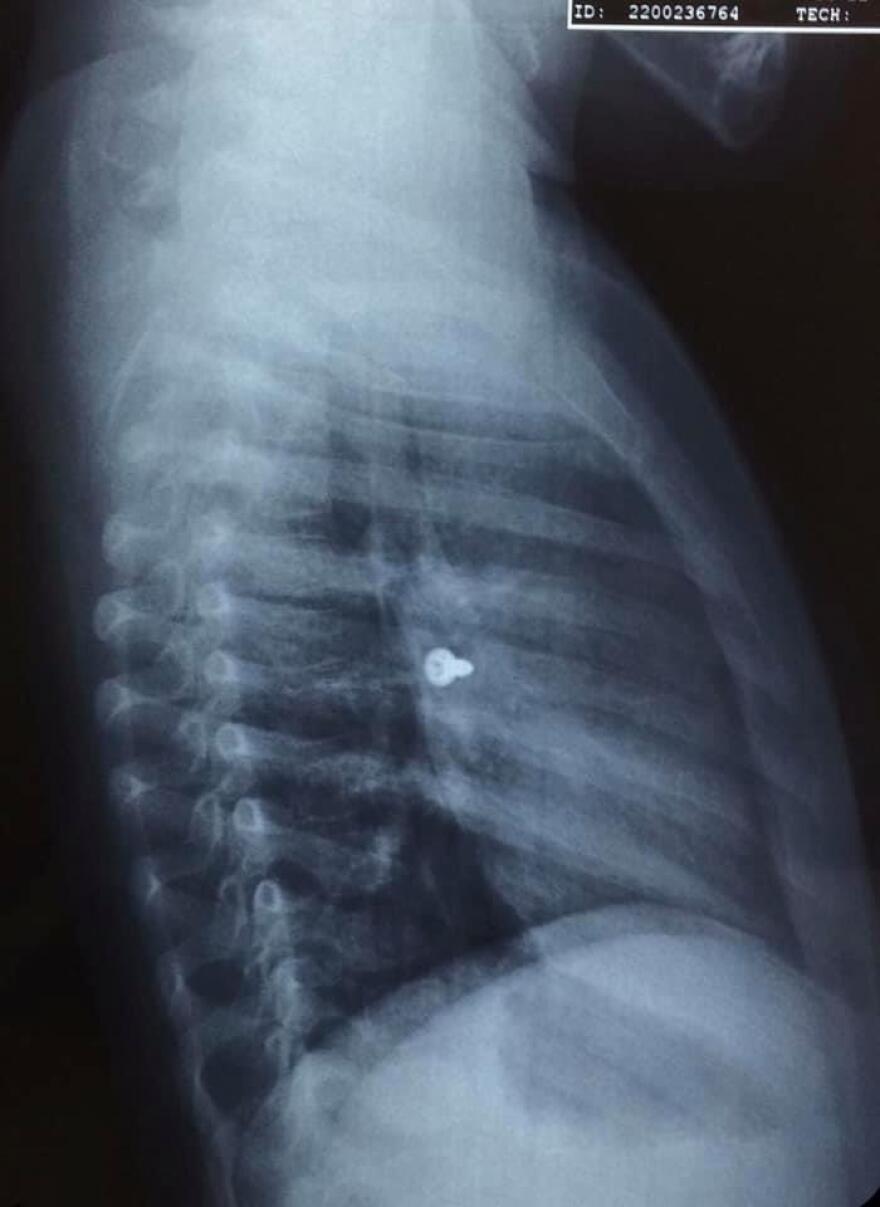

Σοκάρουν οι ακτινογραφίες από ένα κοριτσάκι στην Κρήτη που κατάπιε βίδα, η οποία κατέληξε στον αριστερό του πνεύμονα.

Σύμφωνα με τα όσα έκανε γνωστά ο αναπληρωτής καθηγητής ΩΡΛ της Ιατρικής Σχολής Κρήτης, Μανώλης Προκοπάκης, την Τρίτη μεταφέρθηκε σε νοσοκομείο του Ηρακλείου ένα τρίχρονο κορίτσι το οποίο κατάπιε μία βίδα.

Αμέσως έβγαλε ακτινογραφίες, που έδειξαν πως η βίδα βρισκόταν στον αριστερό του πνεύμονα.

Οι γιατροί οδήγησαν το κορίτσι στο χειρουργείο και μετά από αρκετή ώρα κατάφεραν να αφαιρέσουν την βίδα.

Ο κ. Προκοπάκης σε ανάρτησή του στα social media ανέφερε: «Πολύ επείγον χειρουργείο! Πριν από λίγο. Αφαίρεση βίδας από αριστερό βρογχικό δέντρο τρίχρονου κοριτσιού. Πολύ επικίνδυνο…».